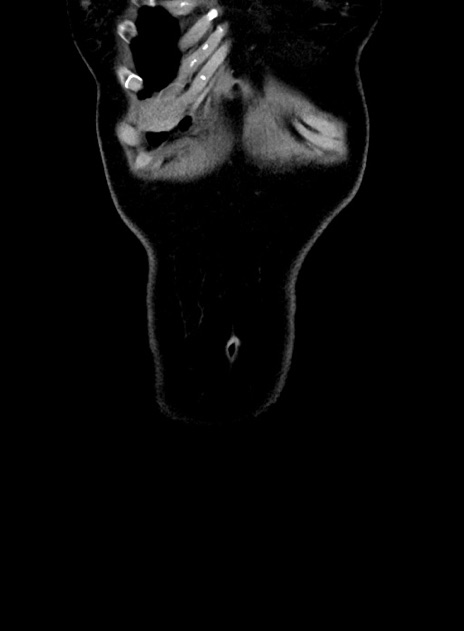

症例9(冠状断像)

症例

【症例】 60歳代女性

【主訴】むかつき、みぞおちの痛み

【現病歴】3日前よりむかつきがあり、食事がとれない。

【既往歴】糖尿病

【身体所見】発熱なし、心窩部圧痛軽度あるも、腹膜刺激症状なし。

【データ】WBC 7400、CRP 1.92